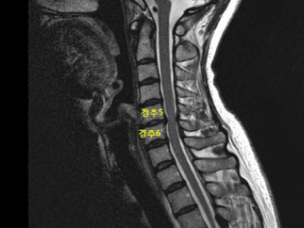

목 디스크란 경추 뼈와 뼈 사이의 추간판 ( 디스크 )이 탈출하였거나 파열돼 경추신경이 자극 또는 압박을 받아 경항부 ( 목 ), 경견부 ( 목과 어깨 ), 견배부 ( 어깨와 등 ), 상지 ( 팔 )에 통증 및 신경학적증상을 나타내는 질환 이고요. 경추는 운동성이 큰부위 이예요.

경추의 디스크는 난폭한 압력을 받으면 돌출하여 척수나 신경근을 억누르게 된다고 합니다. 대부분의 목 디스크는 난폭한 퇴행성 전환 향후에 발생하기 때문에 많은 환자들이 만성적인 경항통 ( 목의 통증 )에 대한 오래전력을 갖고 있다고 한다면가 대다수 이고요. 그럼 이제부터 적극적으로 목 디스크에 좋은 운동을 따져보도록 하겠습니다.